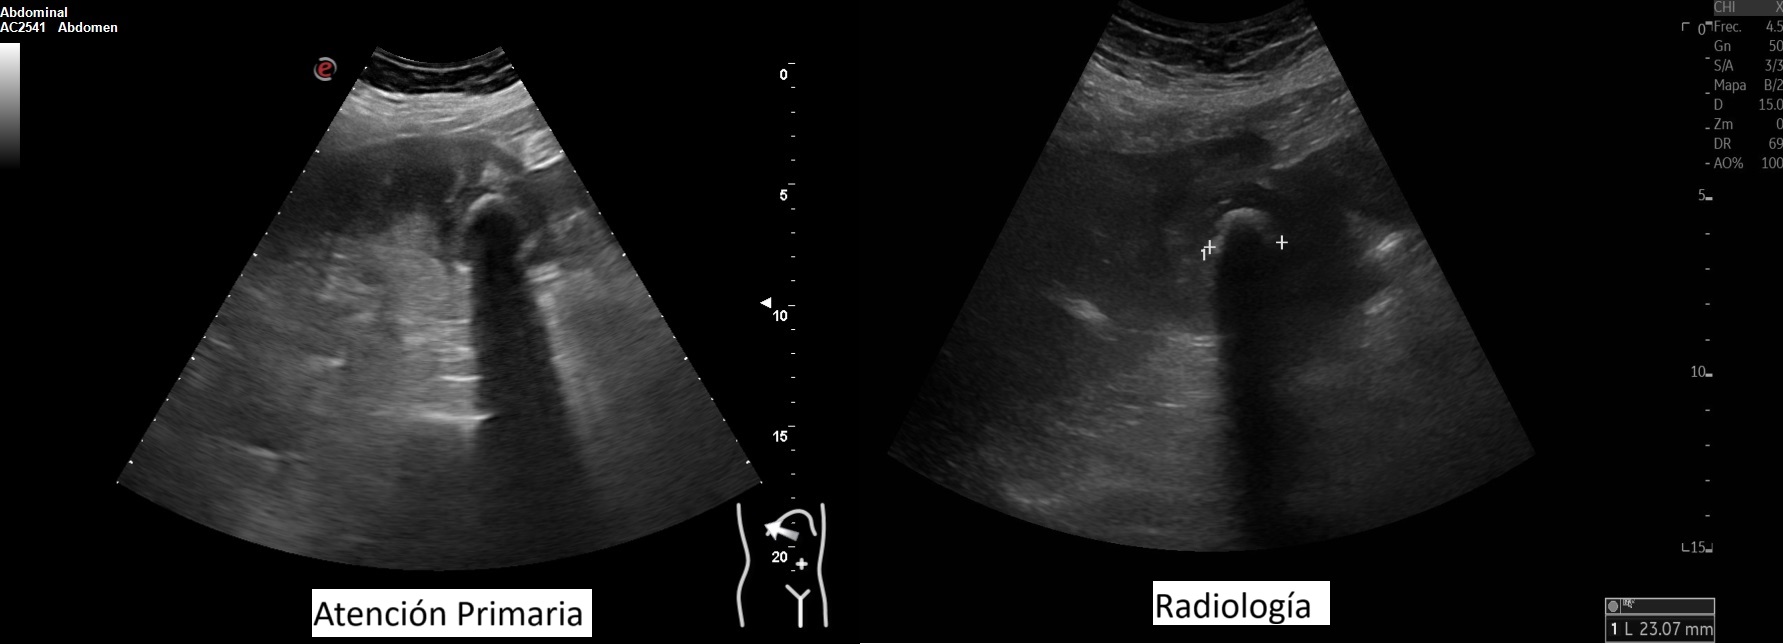

Hallazgos ecográficos

Vesícula biliar desestructurada, de paredes mal definidas con litiasis de 20 mm, que contacta con la pared de la segunda porción duodenal. Porta de tamaño normal. Vía biliar no dilatada.

En los análisis destacaban: GOT 419 GPT 525 FA 373 Bilirrubina 5,3 PCR 184 19.800 leucocitos con neutrofilia. Se realiza tomografía computarizada y nueva ecografía. Se inicia antibioterapia e ingresa con impresión diagnóstica de colecistitis sobre colecsitopatía crónica versus neoplasia vesicular.